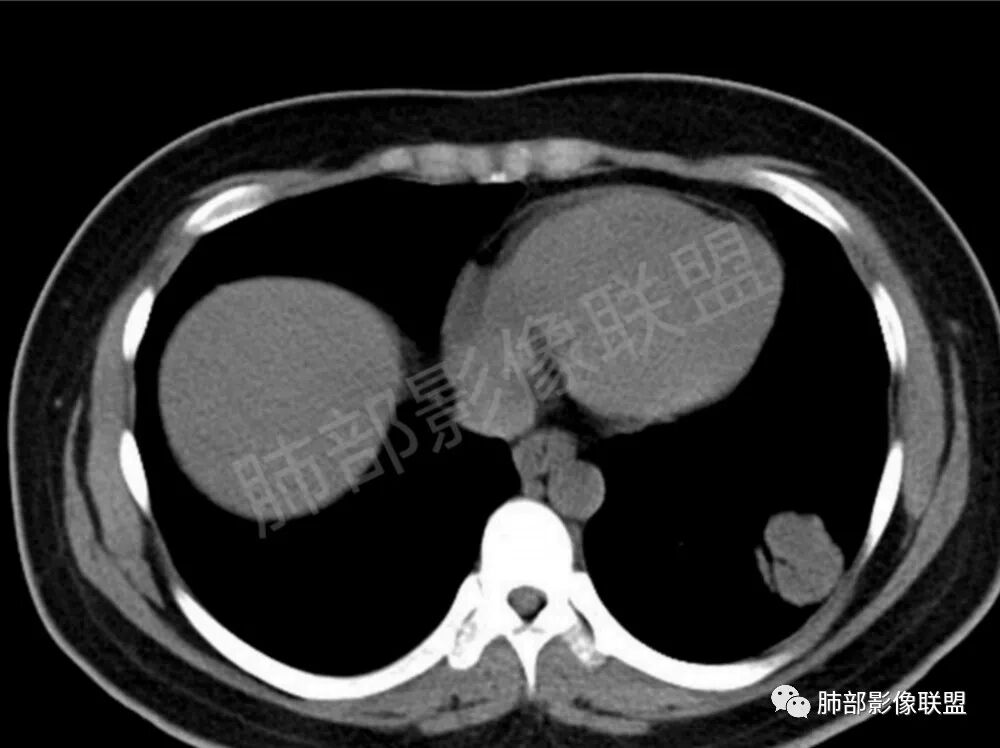

两肺多发结节性,大部分位于胸膜下,部分结节周围可见晕征。局部结节内可见扩张的支气管,纵隔淋巴结大,脾大,22岁男,HIV阳性,常规先考虑隐球菌。鉴别淋巴瘤,结核,马儿。

男,22,半年前咳嗽伴少痰,查HIV阳性,痰查TB阳性,既往有肺部斑片影伴空洞、纵隔淋巴结肿大、脾大。SCC、CA50、CA199、FER增高,此次胸部CT:两肺多发结节影,部分沿血管束分布,部分贴胸膜下,大小不一,密度不一,部分较散、边缘模糊,部分较实、圆钝、周围模糊晕,部分结节有支气管进入穿行自然,部分结节有血管分支自如通过。考虑HI∨相关淋巴增殖类病变,淋巴瘤?LYG?鉴别PC、TB。

青年男性,半年前咳嗽,HIV阳性,结核DNA阳性,肿标糖类抗原和铁蛋白增高。外院影像有纵隔淋巴结增大伴脾大,肺部病灶空洞。现在影像:肺内多发沿支气管分布(有支气管充气征,长轴沿支气管分布)及胸膜下分布(平行于胸膜)的大小不等结节,个别伴有空洞,双侧腋窝淋巴结肿大。纵隔图片不够,是否还有淋巴结肿大未知,脾脏未显示。

1、HIV相关淋巴瘤,有HIV阳性,有纵隔及腋窝淋巴结肿大,肺内病灶沿支气管分布(中轴淋巴间质)及胸膜下分布(周围淋巴间质),有脾大,这个是必须要考虑的。但是原来的影像是肺斑片影伴空洞,又有疑问,需要穿刺明确。

肺淋巴瘤样肉芽肿病( pulmonary lymphomatoid granulomatosis,PLG) 是一种由血管中心性淋巴组织 增生和血管炎性浸润引起的淋巴组织增生性疾病。临床罕见,好发于成年人,也可发生于免疫功能缺陷 的儿童,男性易感( 男女之比>2 ∶ 1) 。由 EB 病毒诱 导,表现为肺部多发结节,胸部 CT 表现与各种感染 性疾病、血管炎、肺癌等难以鉴别。根据EBV阳性B细胞所占比例的不同,该病可分为不同的等级,它们可进展为EBV阳性弥漫性大B细胞淋巴瘤。

影像学缺乏特征性,以支气管血管周围、胸膜下及双肺下叶周边多发结节影最多见,结节易坏死形成空洞,伴有游走性和多变性的特征,结节周围可有磨玻璃样晕征,有时也可见单发结节影、薄壁的囊状阴影或弥漫性浸润影。肺门、纵隔淋巴结肿大少见, 可见胸腔积液和气胸。